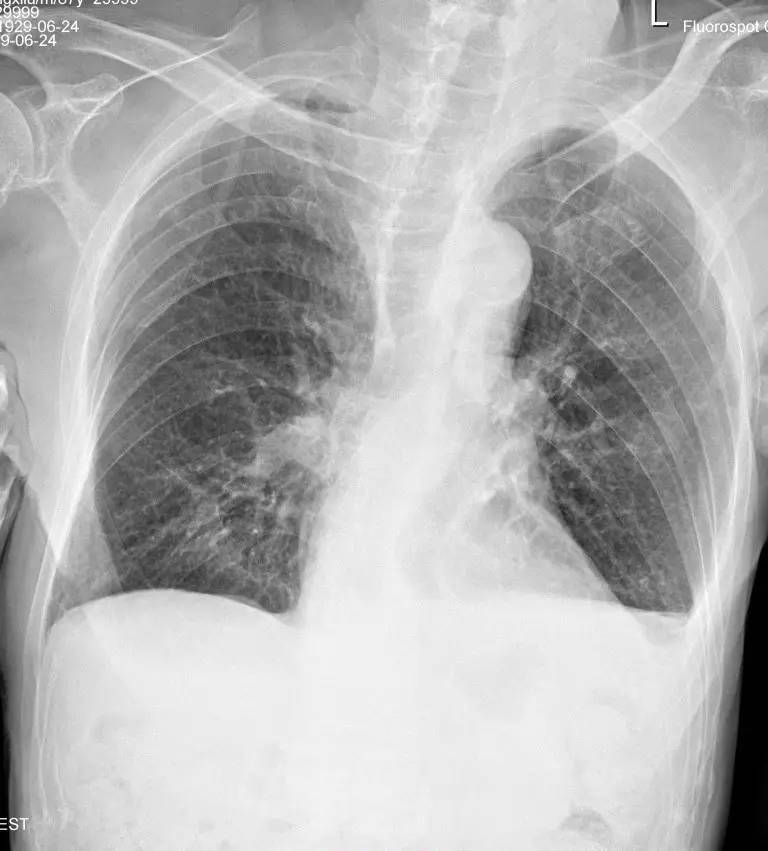

>>>>病例2:男,88y,右侧胸痛月余。

左下肺最有可能的诊断是?

A.包裹性积液

B.胸膜增厚

C.胸腔积液

D.心包脂肪垫